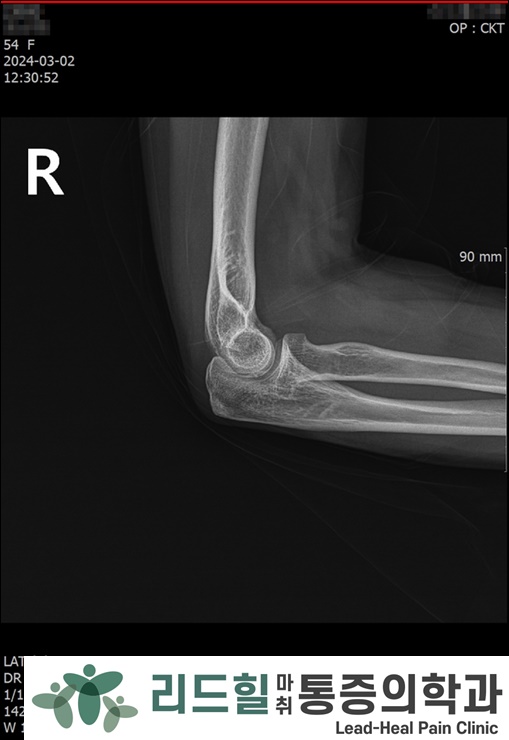

X-ray 검사 결과 : 석회화나 골극, 관절증 등의 이상 소견 없음